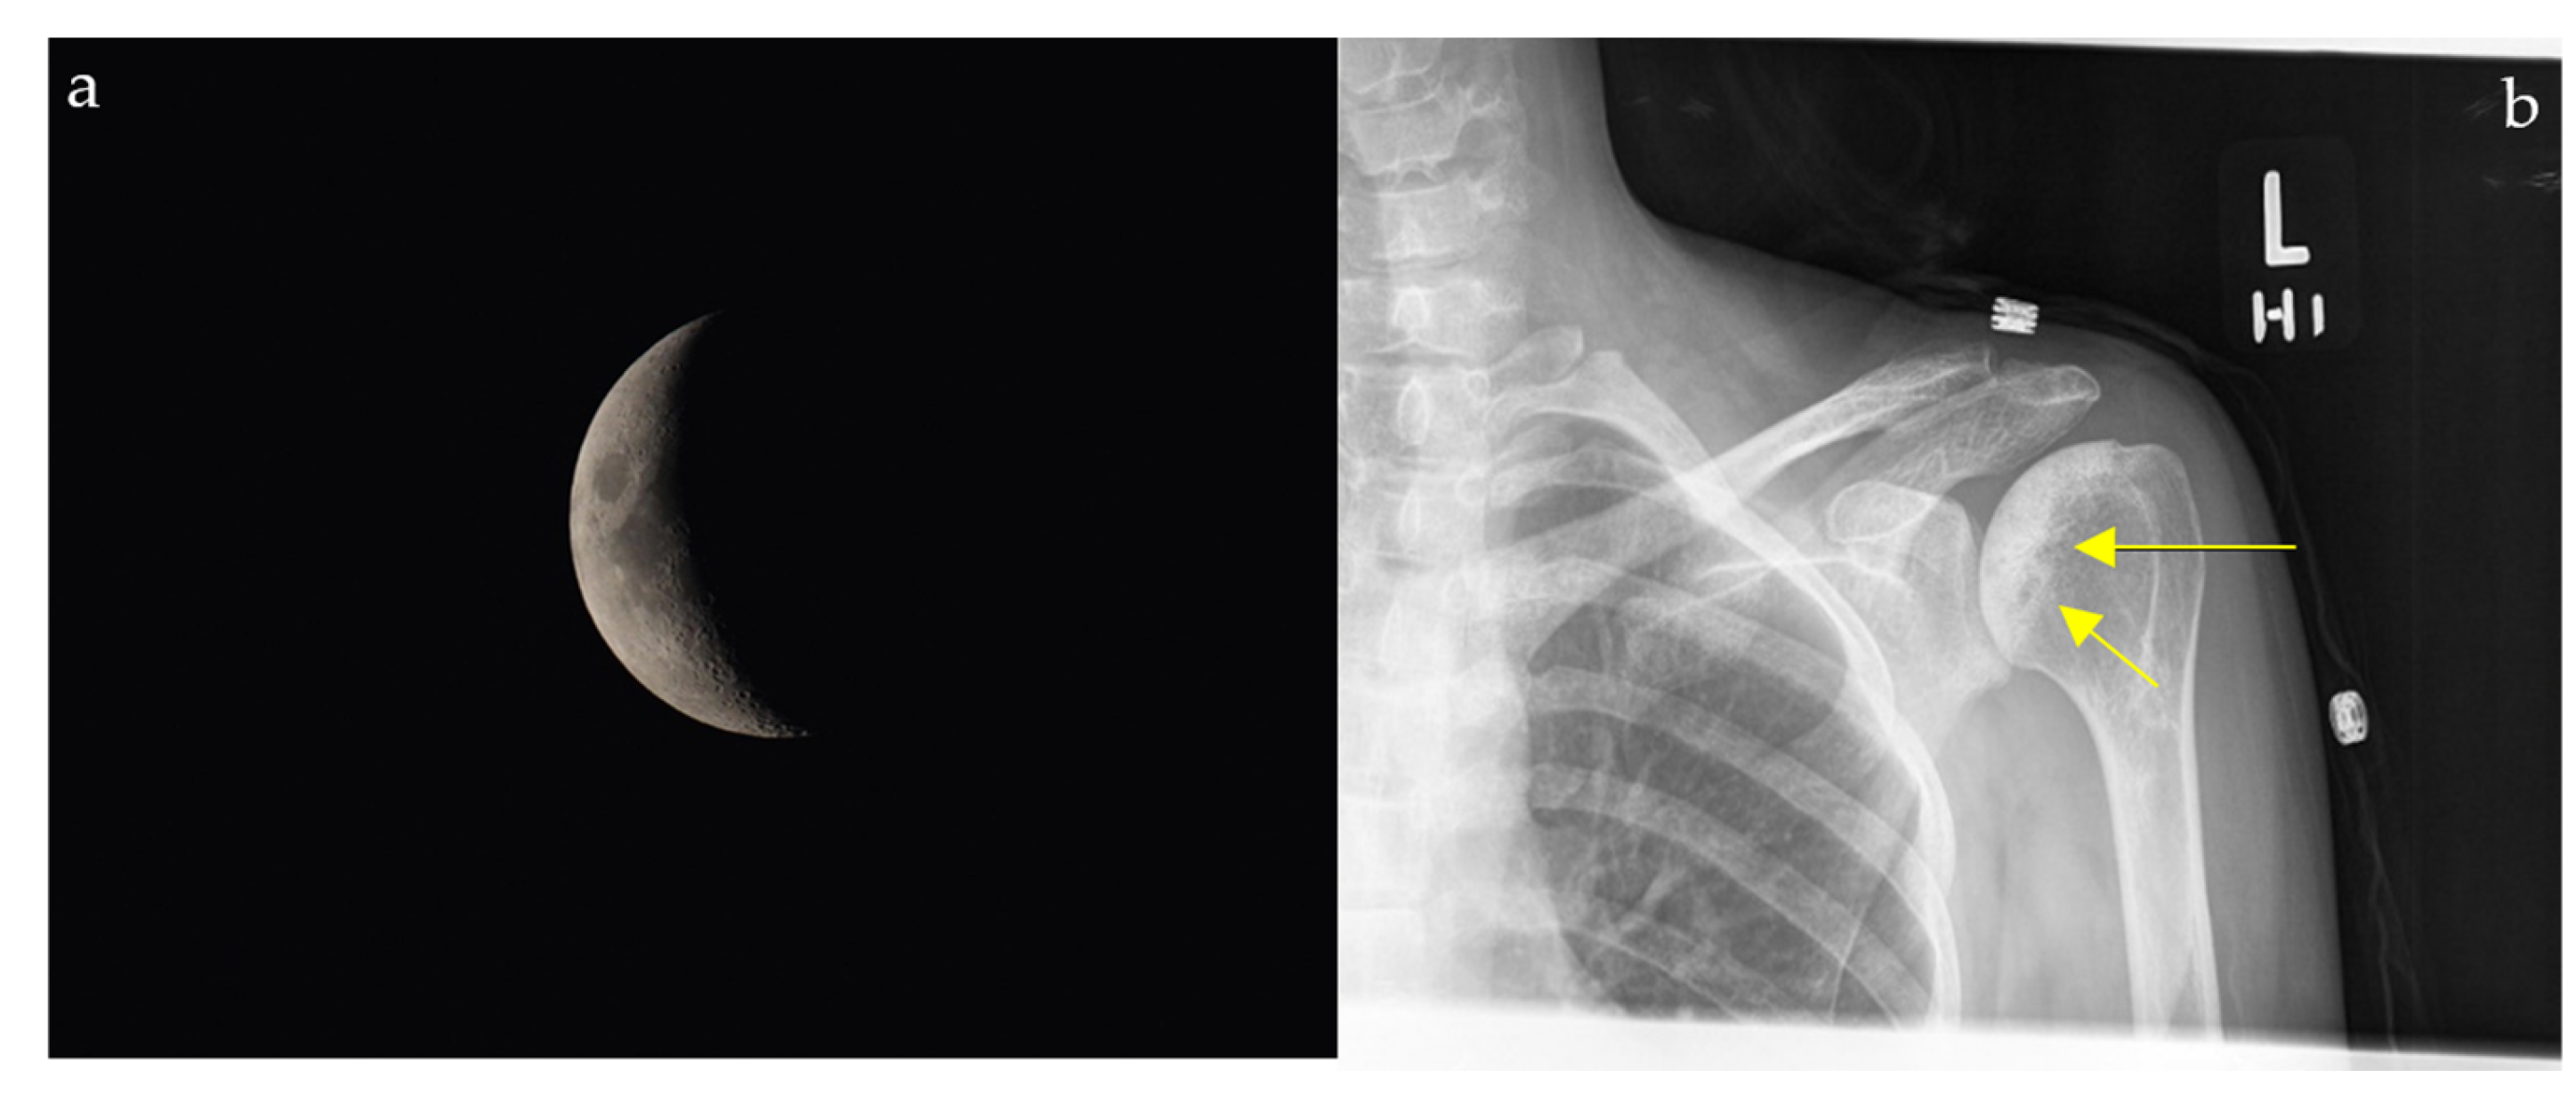

2.4. Loss of Half-Moon Overlap Sign

On a normal anteroposterior shoulder X-ray, there is overlap between the humeral head and the glenoid, giving the appearance of a half-moon (Figure 4b) [23]. In cases of posterior dislocation of the shoulder, the lateral and posterior displacement of the humeral head will result in the loss of this sign. Radiographic signs of posterior shoulder dislocation are more subtle than those of anterior shoulder dislocation, and this may delay diagnosis; hence, the importance of this sign (Figure 4a) [24]. In shoulder trauma with limited external rotation, loss of half-moon overlap on the AP view increases suspicion for posterior dislocation and expedites reduction, preventing missed injuries.

Figure 4.

Plain radiograph of the shoulder showing lateral displacement of the humeral head with respect to the glenoid, losing the half-moon overlap (black arrow) (a), compared to a plain radiograph of a normal shoulder, illustrating the half-moon overlap (b).